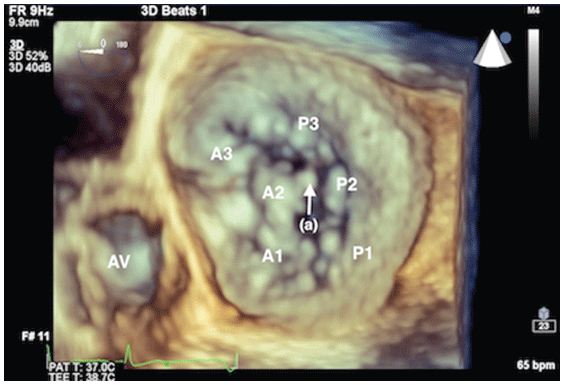

图2:食管中部连合视图显示A2和P2段间严重MR (a)。P1 =二尖瓣后叶P1段;P3 =二尖瓣后小叶P3段;A2/P2 =二尖瓣A2/P2段。

图3:二尖瓣器械及其相应节段三维立体视图,如图A2处连枷节段(a)。AV =主动脉瓣。